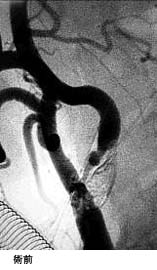

破裂脳動脈瘤に対するGDC(コイル)塞栓術

術後 コイルにより動脈瘤が写らなくなりました。